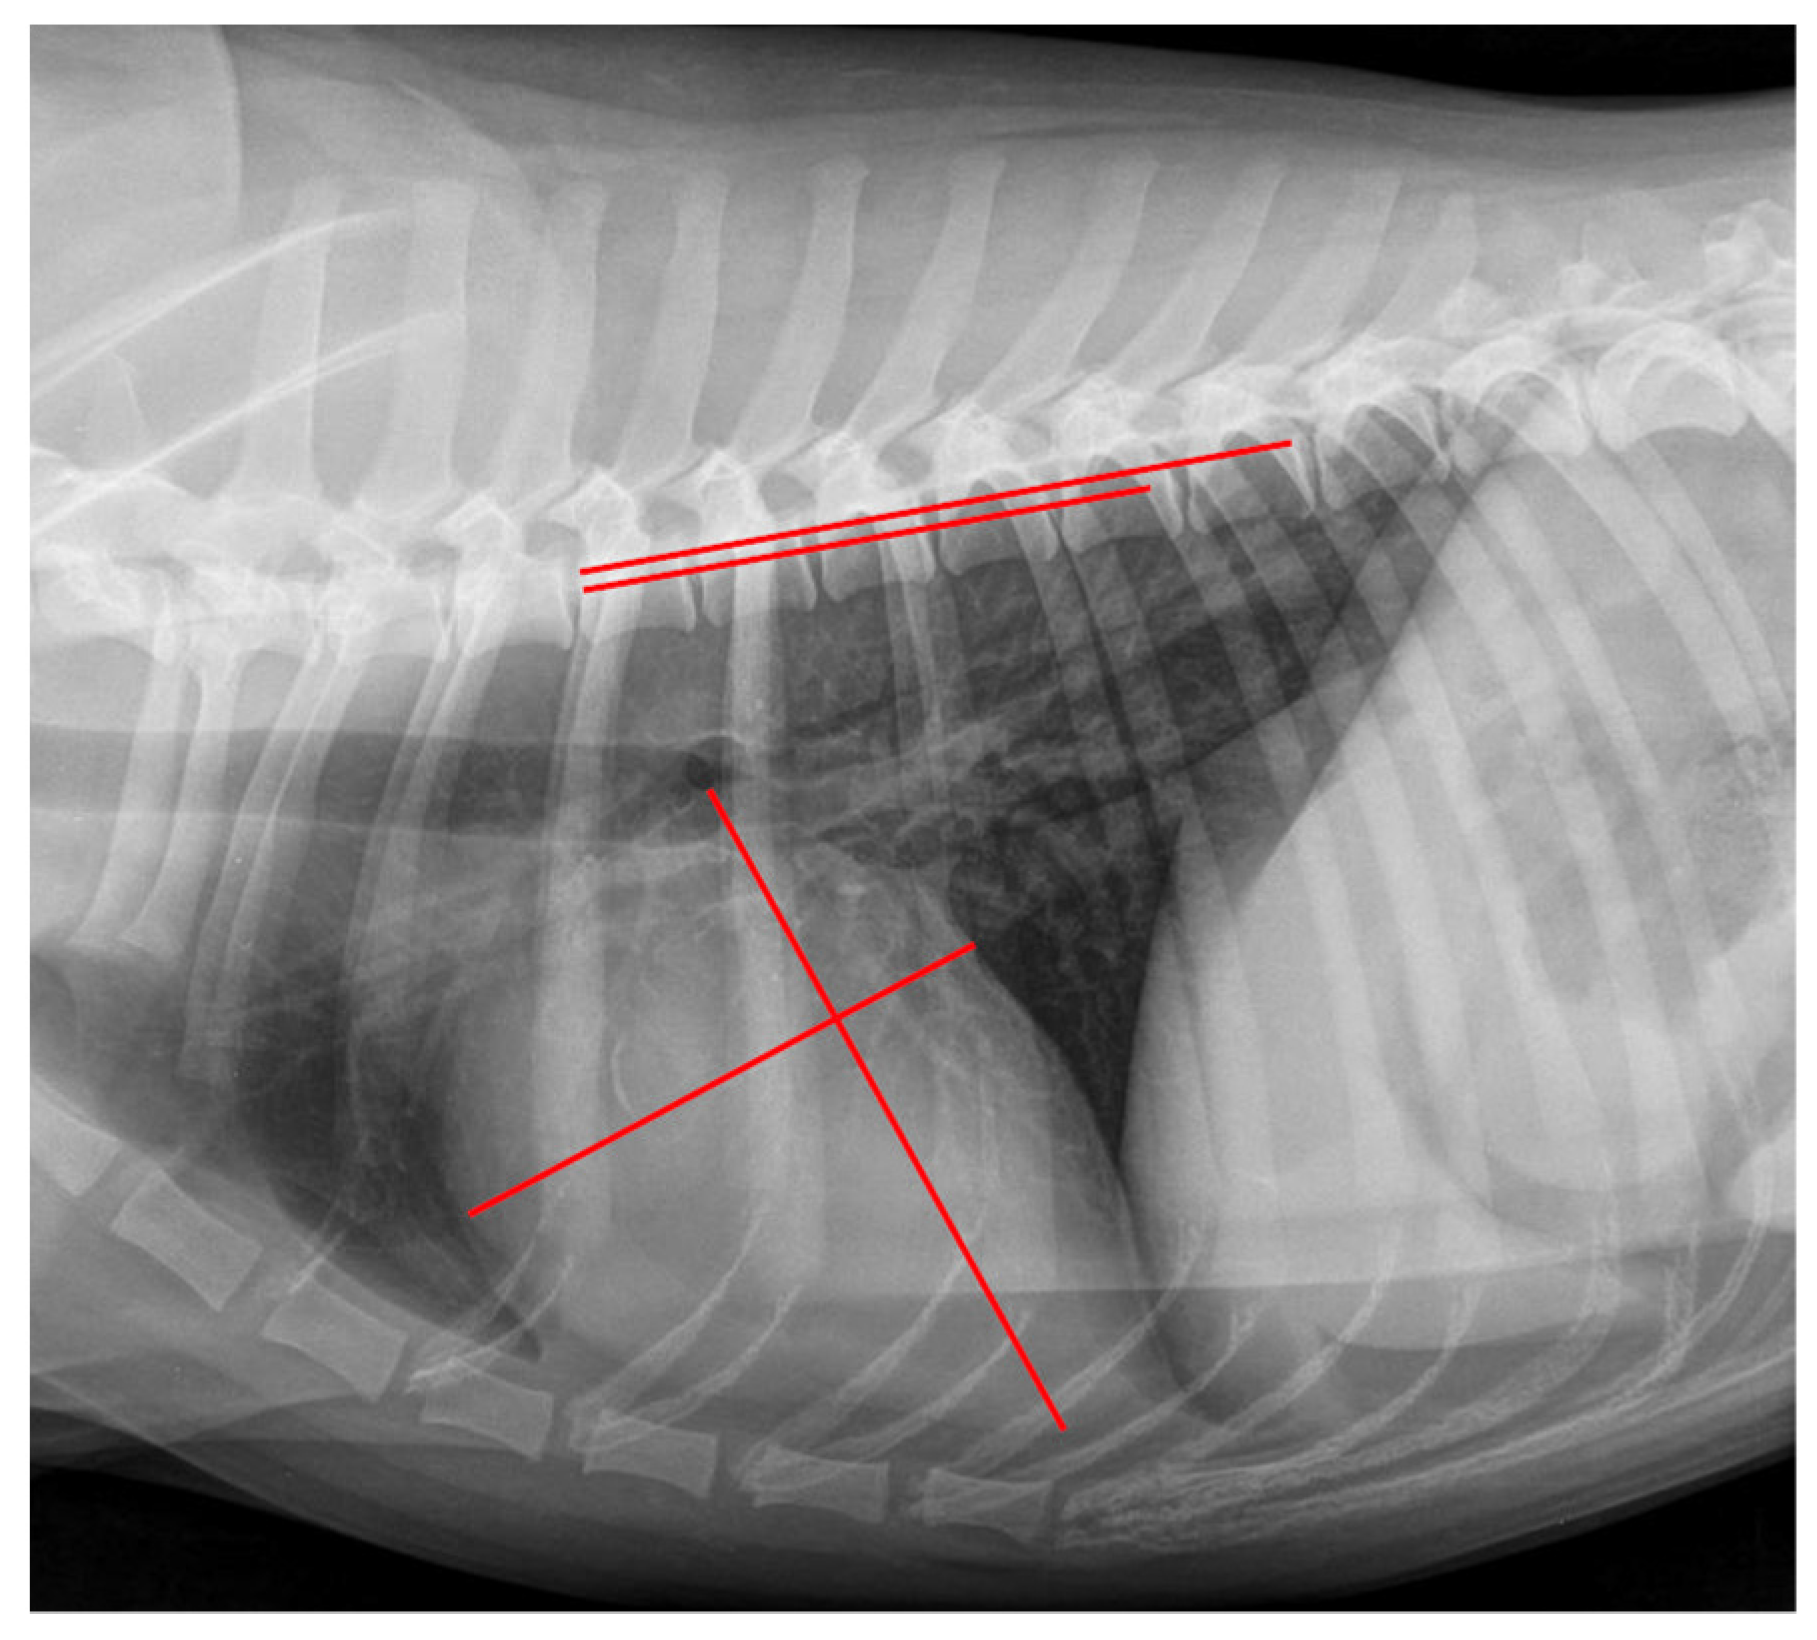

The VHS was obtained as described by Buchanan et al. (1995) [20] and modified according to Jepsen-Grant et al. (2003) [28]. A measurement example can be seen in Figure 1. First, the long axis of the cardiac silhouette was measured from the ventral margin of the carina tracheae to the most distal margin of the cardiac apex. Second, the short axis was drawn at a 90° angle to the long axis and at the level of the ventral intersection of the caudal vena cava and the cardiac silhouette. Afterward, the length of both axes were transcribed onto the vertebral column as described above.

Figure 1.

Measurement example of VHS. Right lateral thoracic radiograph displaying the Vertebral Heart Size (VHS) measurement in a dog of the control group. The long axis was drawn from the ventral margin of the carina tracheae to the most distal margin of the cardiac apex, and perpendicular to the short axis was drawn at the level of the ventral intersection of the caudal vena cava and the cardiac silhouette (red lines on cardiac silhouette). These lines were repositioned onto the vertebral column (red lines on vertebral column) beginning at the cranial margin of the fourth thoracic vertebrae. The VHS was 10.5 vertebral units.